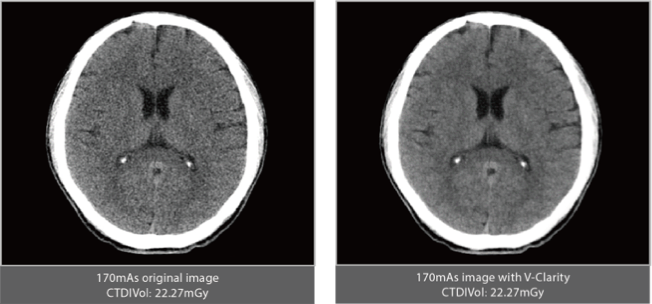

High-power generator delivers high mA output for rapid scanning of complex anatomy and large coverage areas, boosting scan speed while enhancing image signal-to-noise ratio and minimizing artifacts